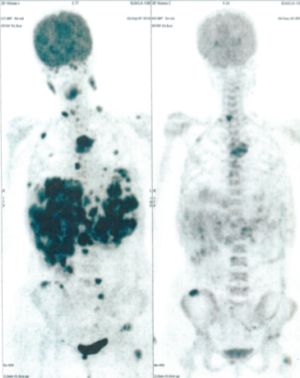

CASE NO: 34 (PERIPHERAL T-CELL LYMPHOMA)

A 50+ year old female has recurrent Peripheral T-Cell Lymphoma that failed all treatment, and it has spread to lymph nodes in the axillary and mediastinal region, and to the lungs. The specialists gave her about 3 months to live. After just one treatment, the axillary/mediastinal nodes and the lung lesions are gone. One set of pictures shows the lymph nodes, and the other set of pictures show lung lesions. The picture on top is BEFORE TREATMENT, and the picture below is AFTER TREATMENT.

CASE NO: 34 AFTER TREATMENT

CASE NO: 35 (SMALL CELL LUNG CANCER)

A 50+ year old man has quite extensive small cell lung cancer on the right side, that has also spread to the liver. This cancer is reputed to be very difficult to treat, and it has failed all cancer treatment. After some treatment, all the cancer in the right lung and liver are gone except for a smaller one remaining in the right lung. Treatment is continuing.